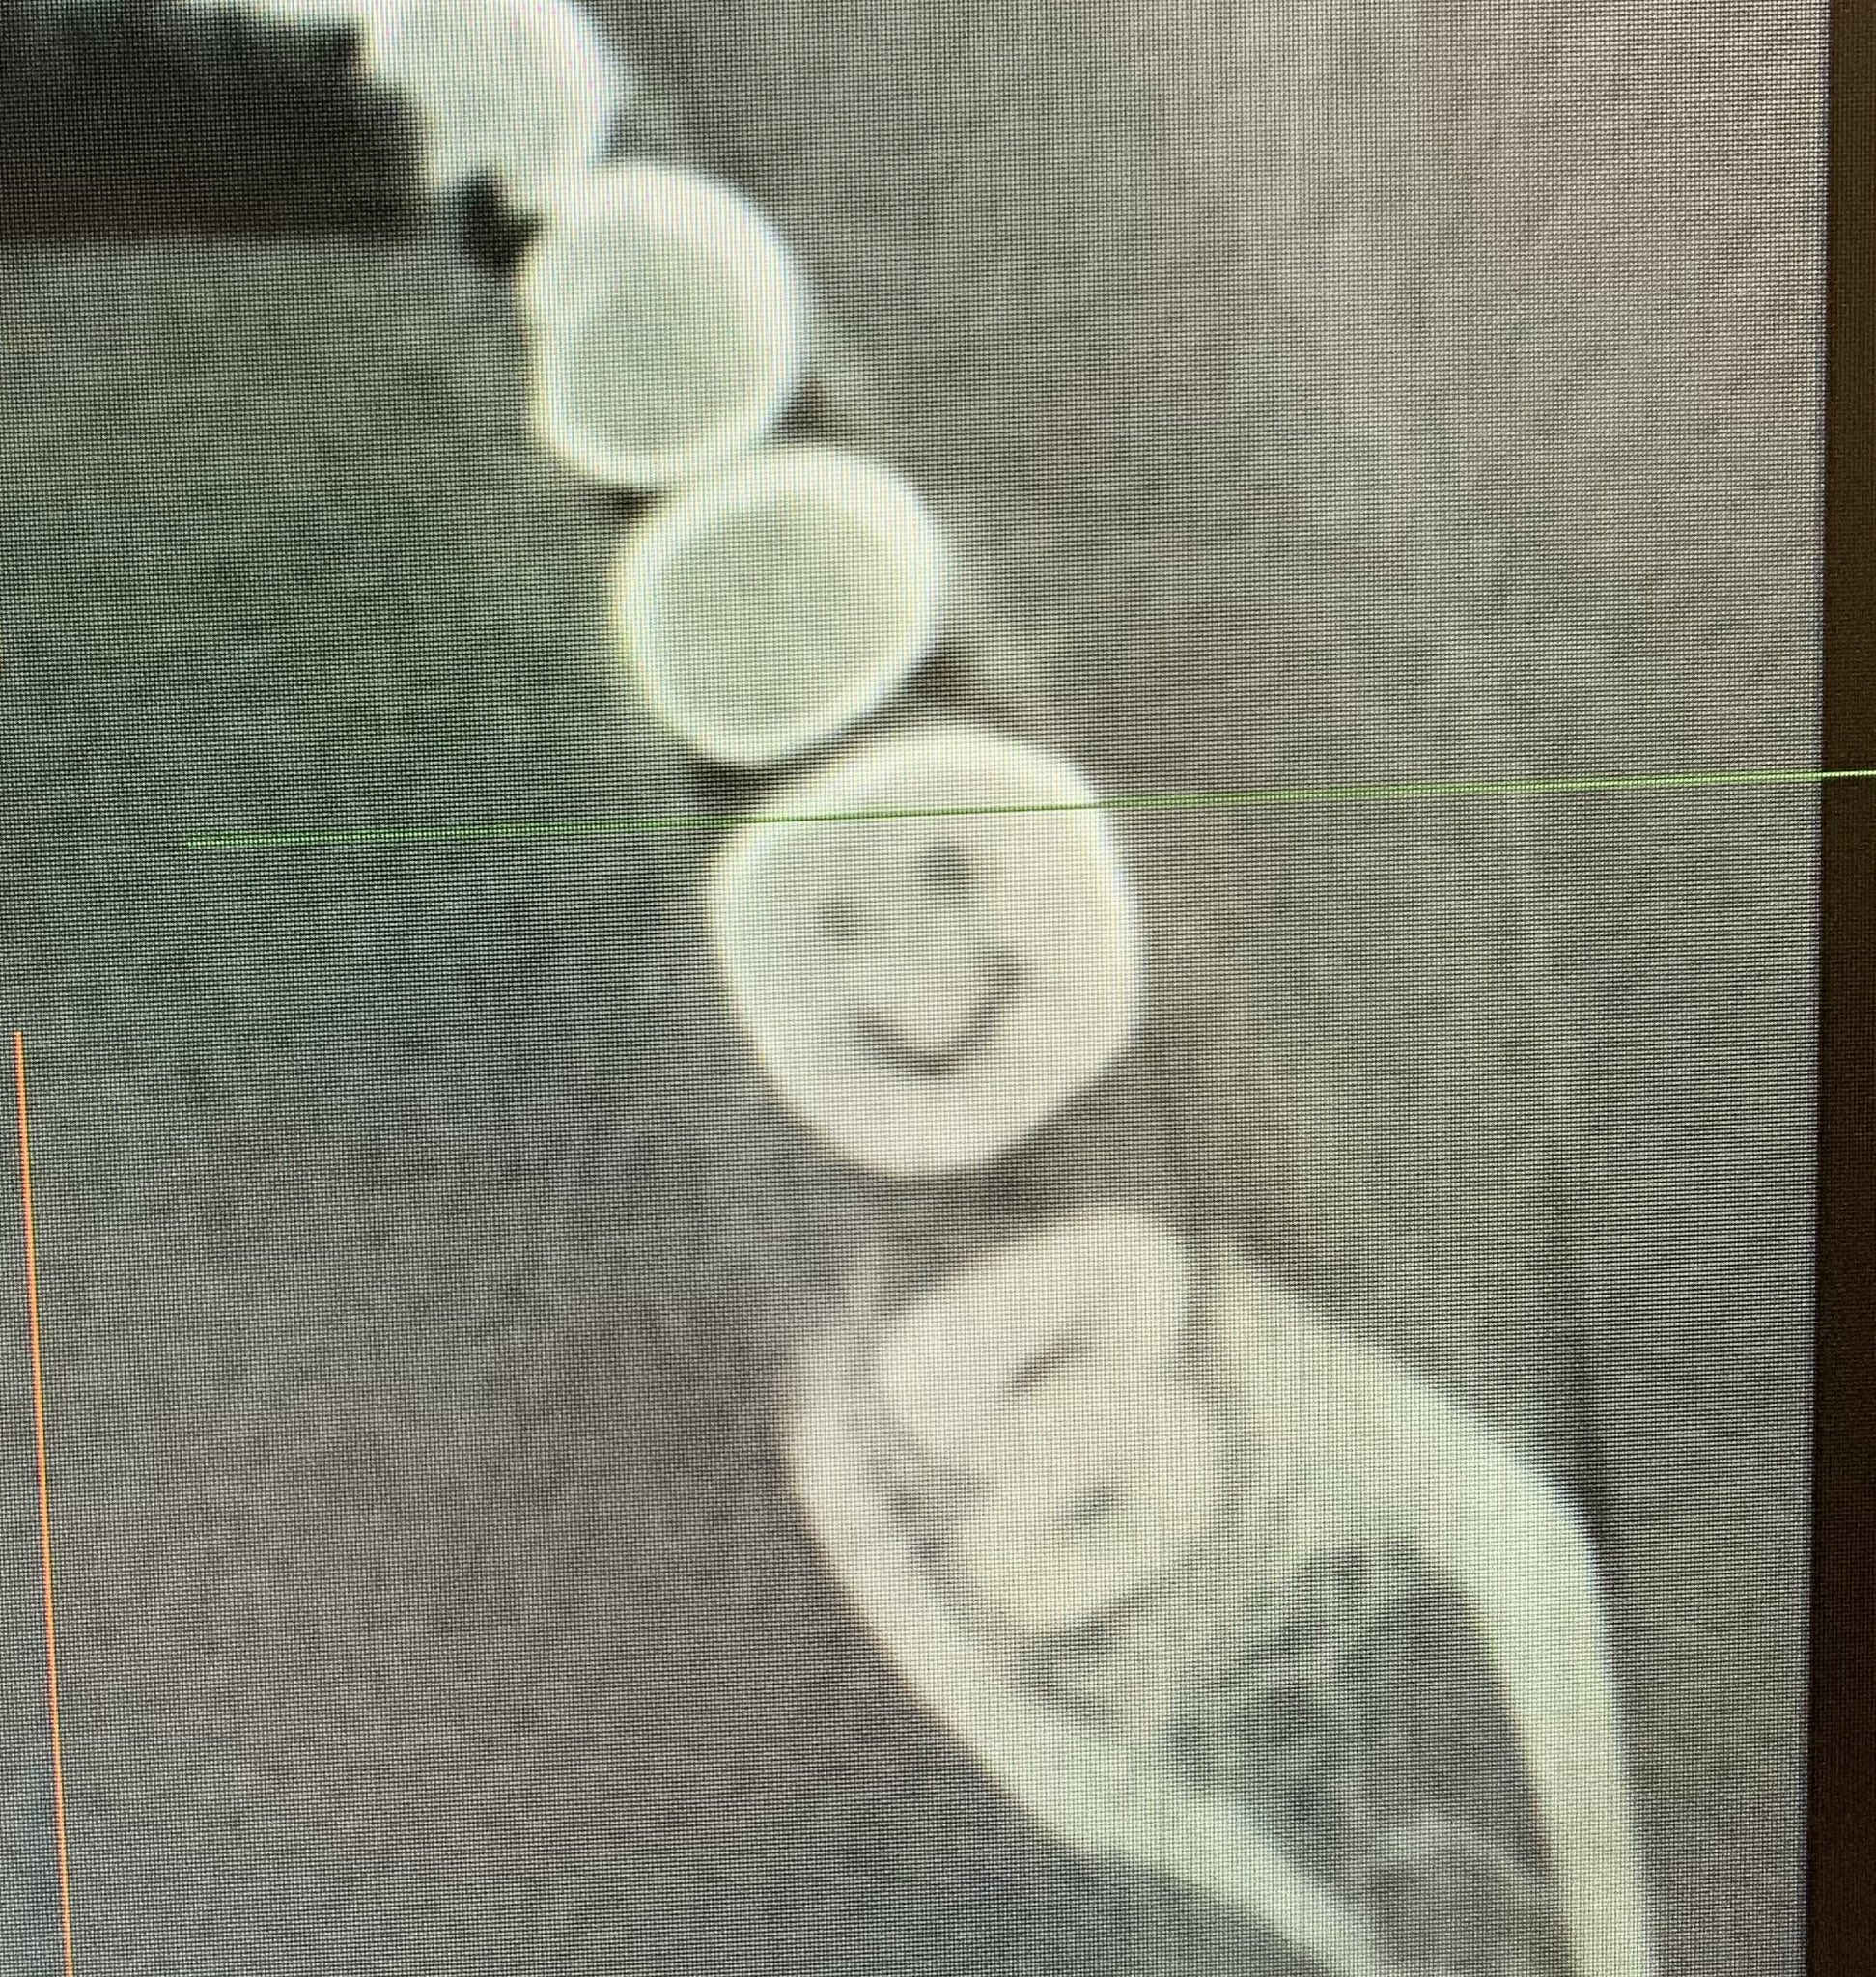

ほら、歯も笑ってますわ!と見せてもらったら良い顔してましたわ

親知らず抜いた……先生が比較的簡単に抜けました。ほら、歯も笑ってますわ!と見せてもらったら良い顔してましたわ pic.twitter.com/aiBt4IECIE— U井T吾 (@it_ui) March 5, 2021 下のやつもこんな風...